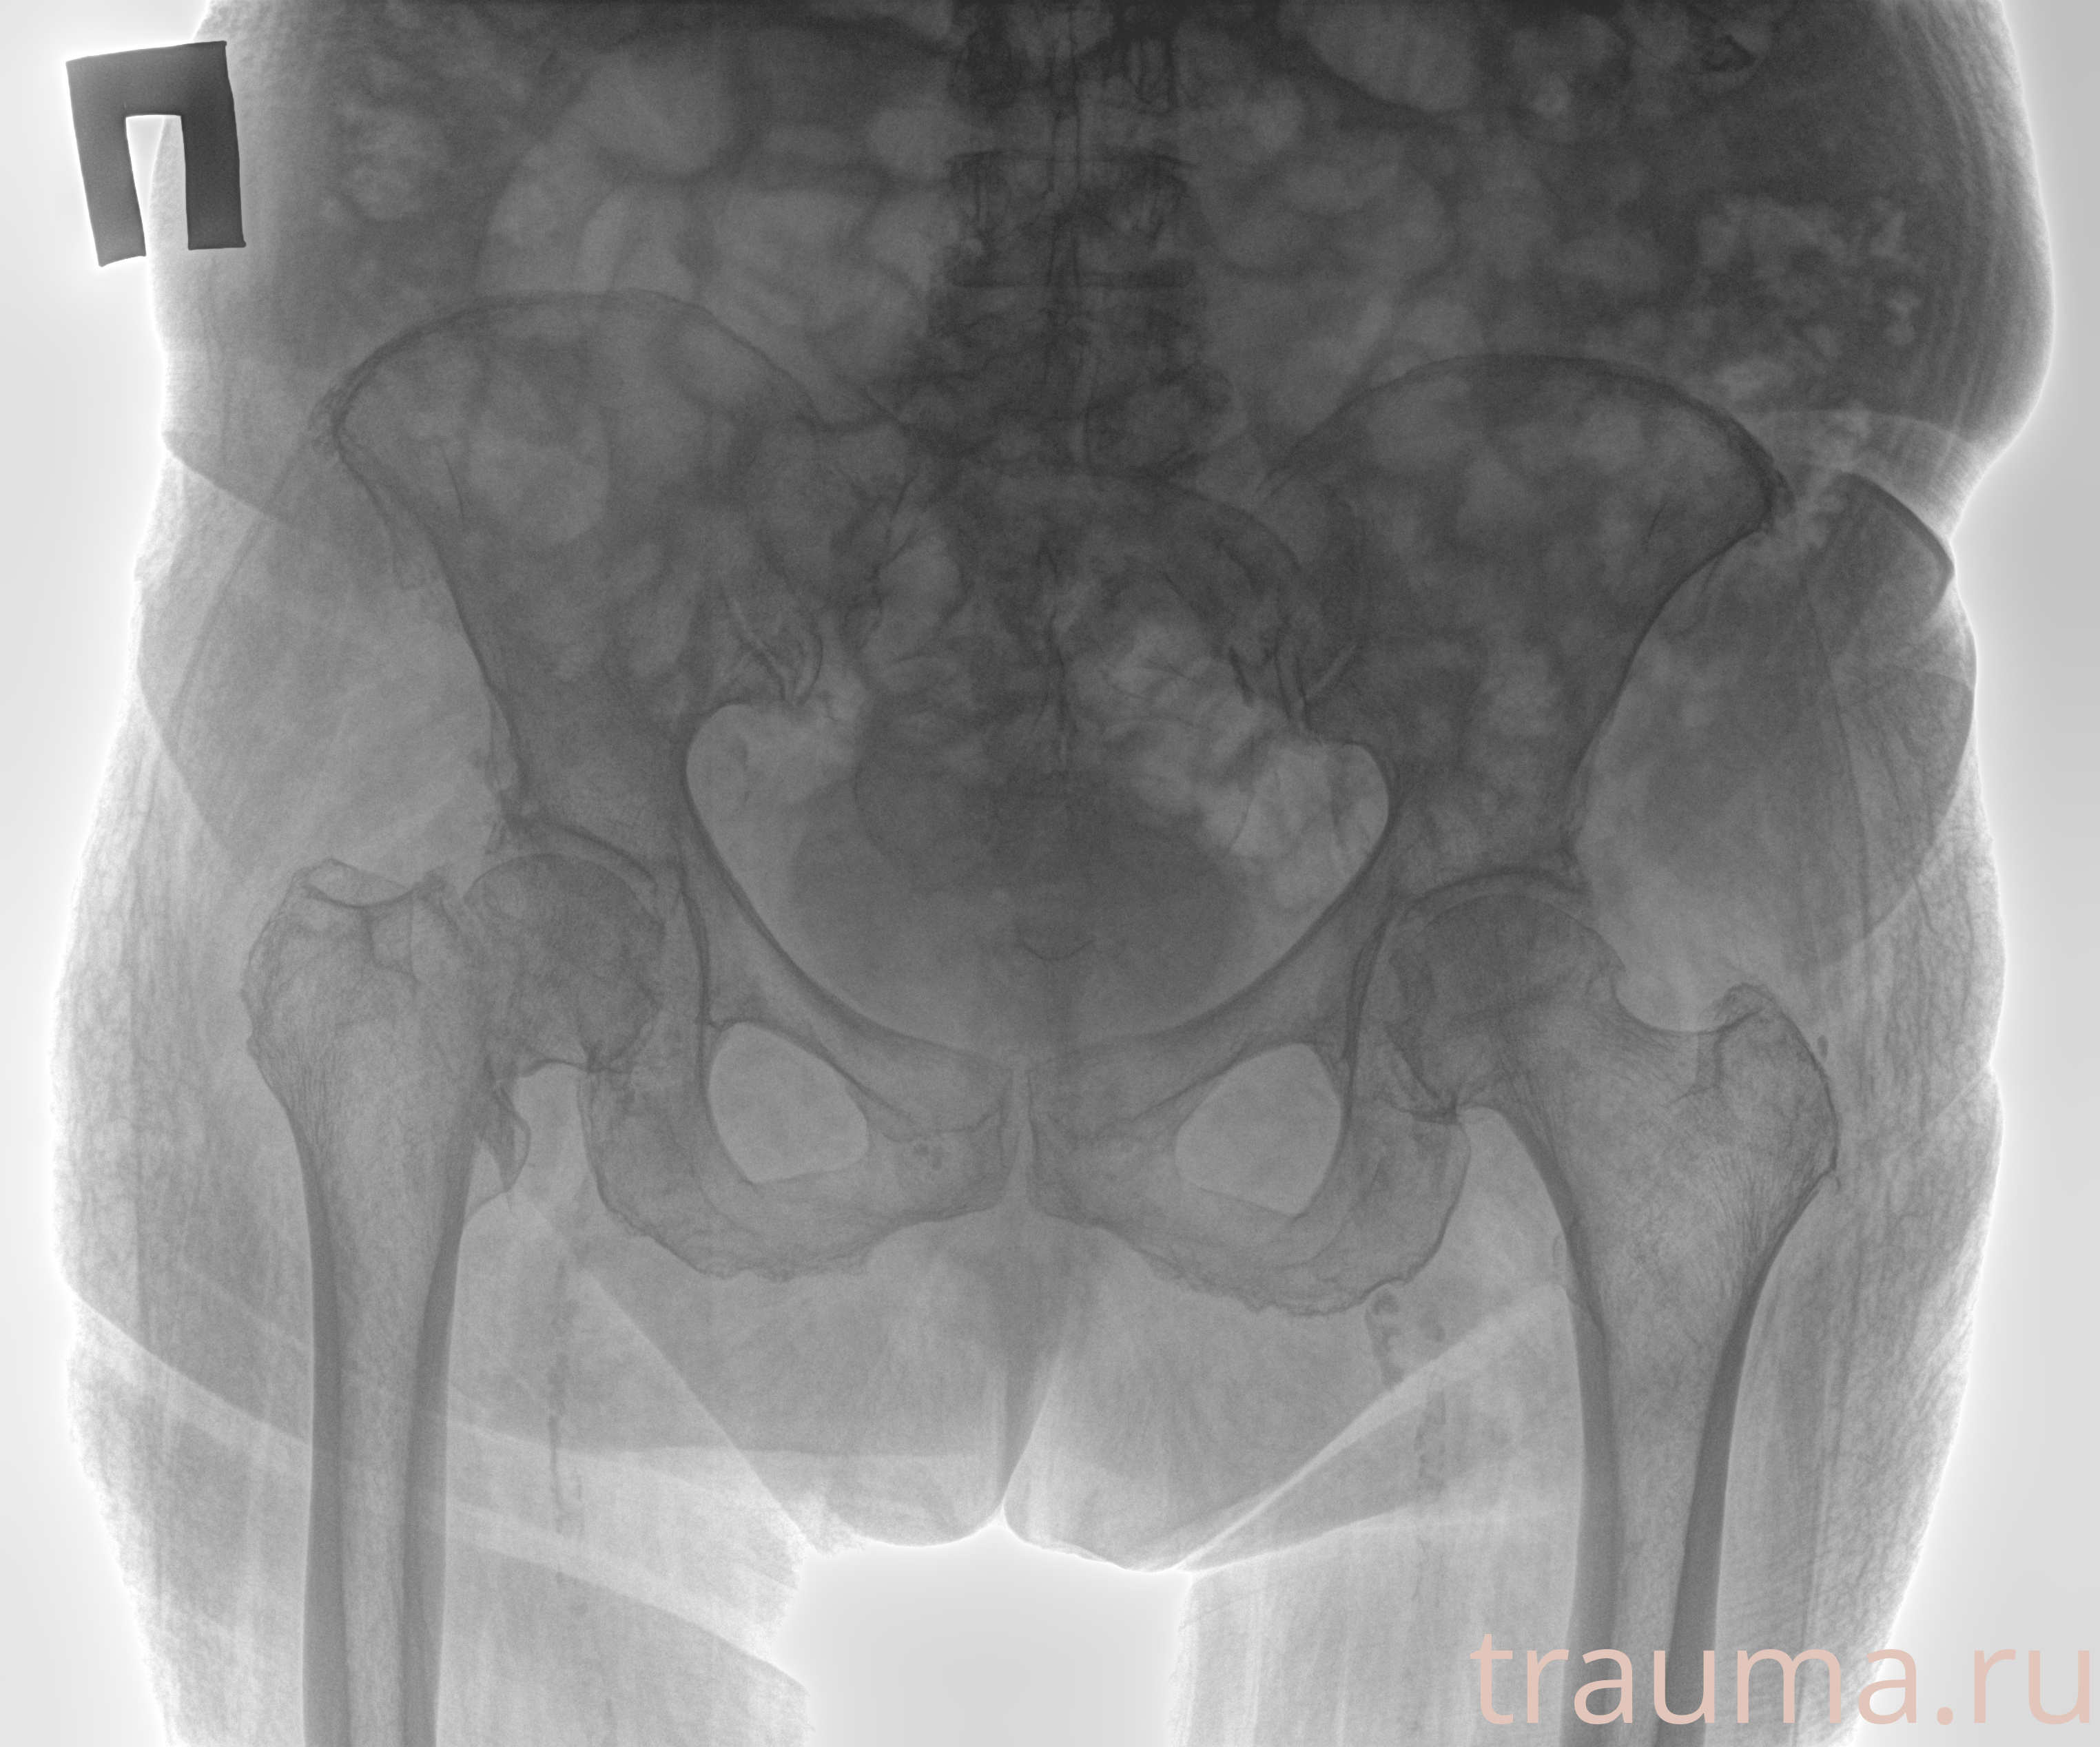

Рентгенограммы

Рентген на дому: по вашему адресу приезжает врач-рентгенолог, травматолог-ортопед с мобильным рентгеновским аппаратом, проводит диагностику травмы или заболевания, делает необходимые рентгенограммы, дает рекомендации по дальнейшему лечению. Получить качественные снимки в домашних условиях возможно благодаря уникальной методике, разработанной МосРентген Центром для института  Склифосовского